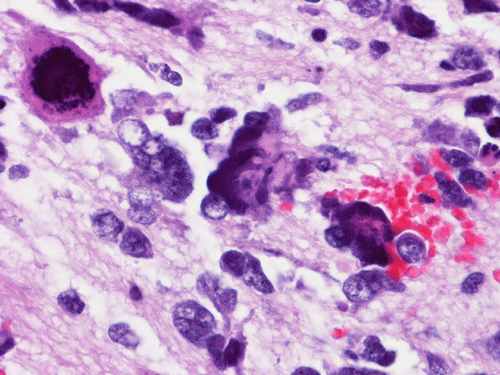

The entire specimen was submitted for histologic examination. The bulk (over 99%) of the tumor was composed predominantly of mature intestinal elements (Panel A, B, and C) and skin, respiratory type mucosa, cartilage, and small amount of mature neural parenchymal tissue of the central nervous system (Panel D and E). Neither immature nor malignant elements are present. Small microscopic foci of well demarcated, neural parenchymal tissue with increased atypia (arrow in panel F) are noted. On higher magnification (Panel G and H), these areas contain large, bizarre appearing cells with dark chromatin but no prominent nucleoli. There are also scant multinucleated cells and mineralized substances (arrow in Panel H). Another example of these foci is illustrated in Panel I, J, and K. These atypical foci comprised less than 1% of the volume of the tumor. They are all microscopic in size and show no evidence of expansion or invasion into the surrounding tissue.

The foci of neural parenchymal tissue with atypia raised the concern for malignancy. The atypical foci are all microscopic in size and well demarcated. They do not invade into the adjacent tissue. Although large atypical nuclei are noted, there is no prominent nucleoli. These changes are more consistent with ancient changes (degenerative atypia) or resulted from the chemotherapy prior to the resection. Identification of mineralized tissue is an additional features to confirm the benign biological potential of these foci. These foci are atypical but not embryonal and must be distinguished from immature element. With this token, the tumor is a mature teratoma but not an immature teratoma. Please see the discussion below for growing teratoma syndrome. This case is also unusual for an elevated alpha fetal-protein in serum with a lack of yolk sac tumor component in the tumor. Please see the discussion below for discussion.